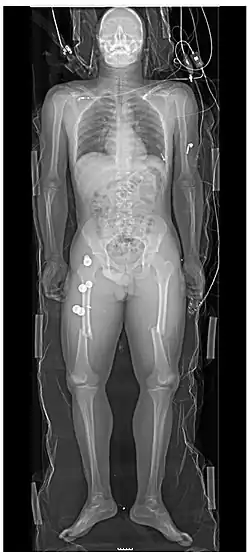

Extremities

A projectional radiograph of an extremity confers an effective dose of approximately 0.001 mSv, comparable to a background radiation equivalent time of 3 hours.[16]

Certain suspected conditions require specific projections. For example, skeletal signs of rickets are seen predominantly at sites of rapid growth, including the proximal humerus, distal radius, distal femur and both the proximal and the distal tibia. Therefore, a skeletal survey for rickets can be accomplished with anteroposterior radiographs of the knees, wrists, and ankles.[20]